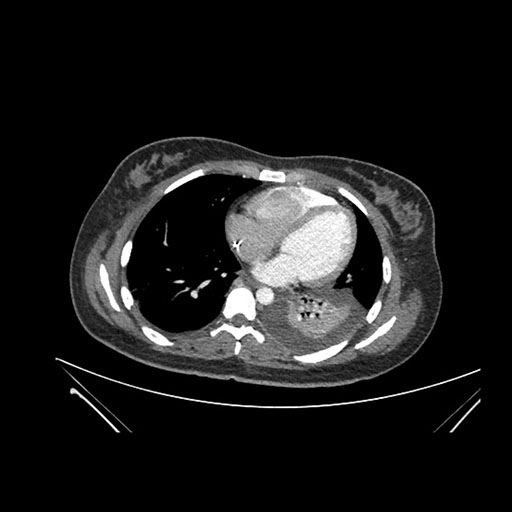

Axial Arterial

Axial Venous

Imaging analysis

Based on initial findings, which issue(s) would you be most concerned about?